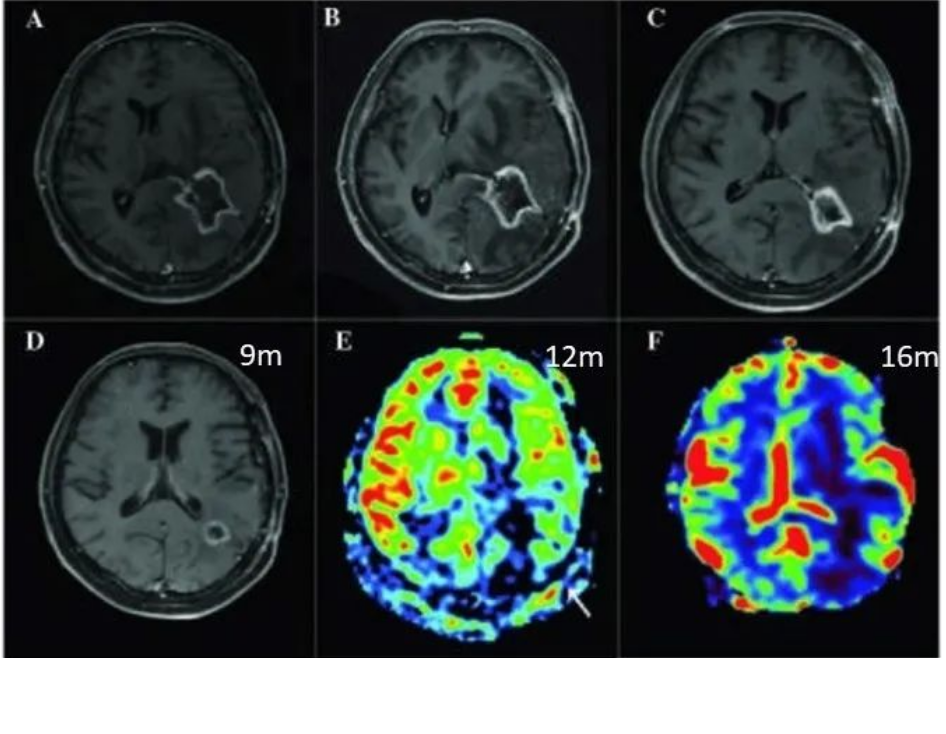

4.PWI灌注加权成像:可定量普股不同的脑血流动力学变量,如相对脑血容量rCBV等,rCBV是新生血管生成的影像学标志物。术后胶质瘤复发ASL和DSC的rCBV明显高于放射性坏死灶。